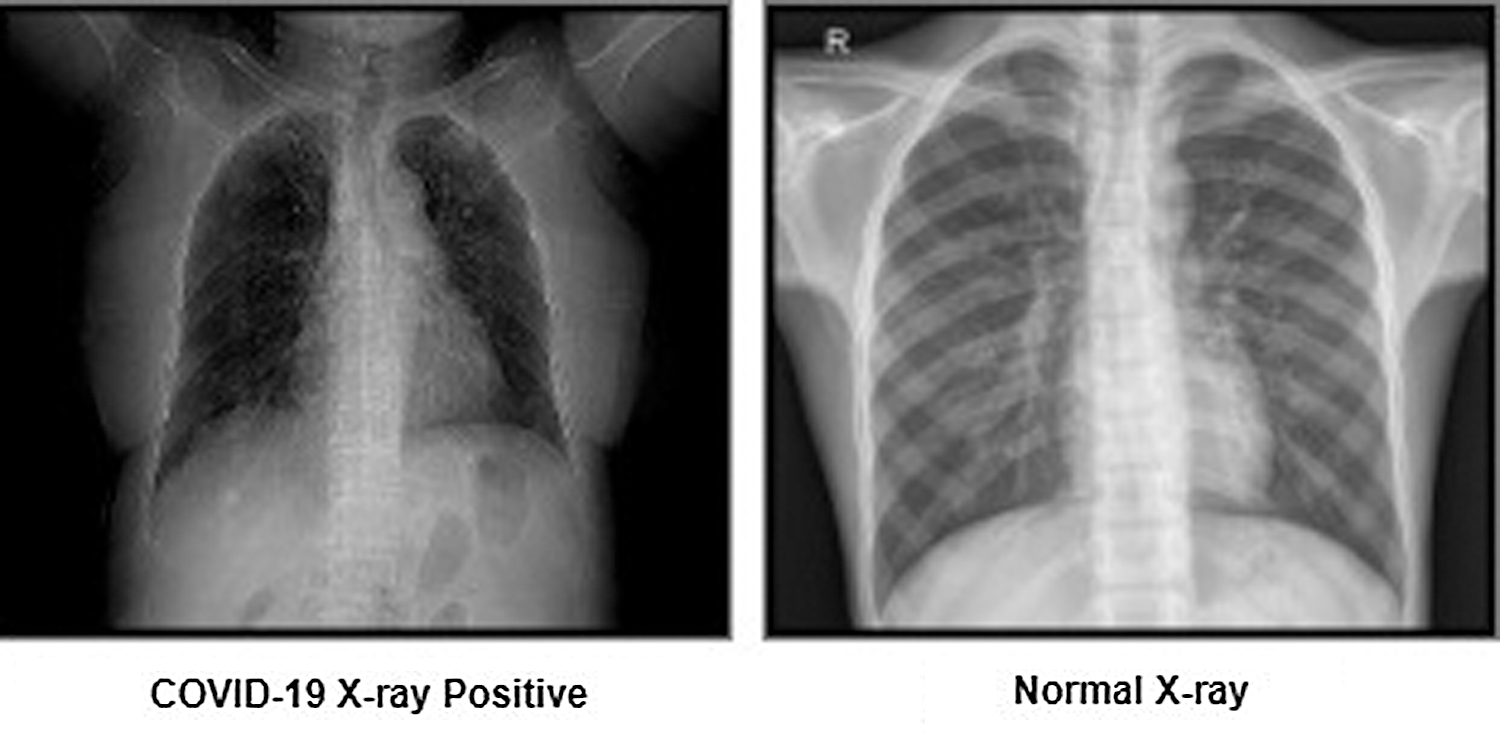

After collecting the COVID-19 images, the X-rays were categorized for each patient. As mentioned, for this paper only two corpus labels categories were created. As such, the researchers used healthy patient X-rays alongside COVID-19 patient images. The dissimilarities between normal X-rays and COVID-19 X-rays were defined as clear and fuzzy chest X-rays, respectively. Fig. 3 provides an example of both X-ray image categories.

Figure 3: Representation of corpus labels